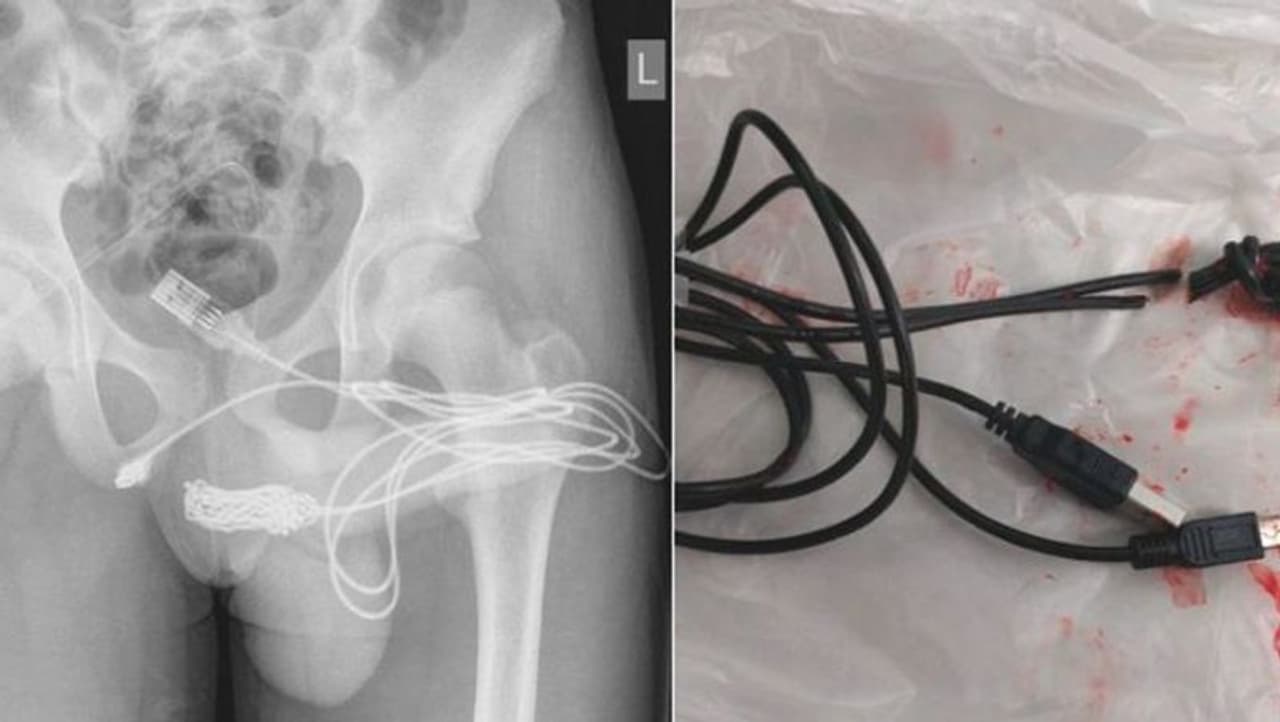

இதனால், சிறுவனின் சிறுநீரில் ரத்தமும் வரத் தொடங்கியிருக்கிறது. இதனையடுத்து, சிறுவனின் தாயார் மருத்துவரிடம் அழைத்து சென்றிருக்கிறார். அப்போது, மருத்துவமனையில் அறையில் இருந்து சிறுவனின் தயார் வெளியே சென்றதும் நடந்ததை மருத்துவர்களிடம் கூறியிருக்கிறார். யூஎஸ்பி கேபிள் இருபுற போர்ட்களும் சிறுவனின் சிறுநீர்க்குழாய் பகுதியில் நீண்டு கொண்டு இருப்பதும், ஏகப்பட்ட முடிச்சு போடப்பட் முடிச்சுகள் இருந்ததால் உலோக கம்பியை கொண்டு கேபிளை அகற்றுவது கடினமான வேலையாக இருந்ததால் அறுவை சிகிச்சை செய்ய வேண்டிய கட்டாயம் ஏற்பட்டது.

பின்னர் அறுவை சிகிச்சை மூலமே அதை வெளியே எடுக்கப்பட்டது. அப்போது தான் தெரியவந்தது அவனது ஆண் குறிக்குள் 70 செ.மீ அளவு உள்ள இருந்தது. இதனையடுத்து, மருத்துவர்களின் கண்காணிப்பில் வைக்கப்பட்டிருந்த சிறுவன் வீட்டுக்கு அனுப்பி வைக்கப்பட்டார்.